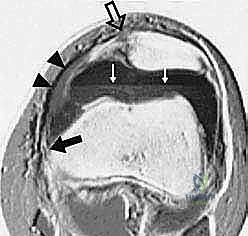

Advanced cross-sectional imaging, specifically MRI and occasionally CT, is indispensable. Axial CT or MRI is used to accurately measure the TT-TG offset, ensuring it falls within the acceptable range (< 15-20 mm) for an isolated MPFL procedure.

However, MRI is the primary modality for evaluating the soft-tissue envelope. We scrutinize the T2-weighted axial and coronal sequences to identify the exact location of the MPFL failure. We look for the classic "wavy" appearance of a detached ligament, surrounding edema, and the presence of a distinct stump at the patellar margin.

Crucially, the MRI must be reviewed for concomitant articular cartilage damage; osteochondral loose bodies originating from the medial patellar facet or the lateral femoral condyle are common and must be addressed concurrently.